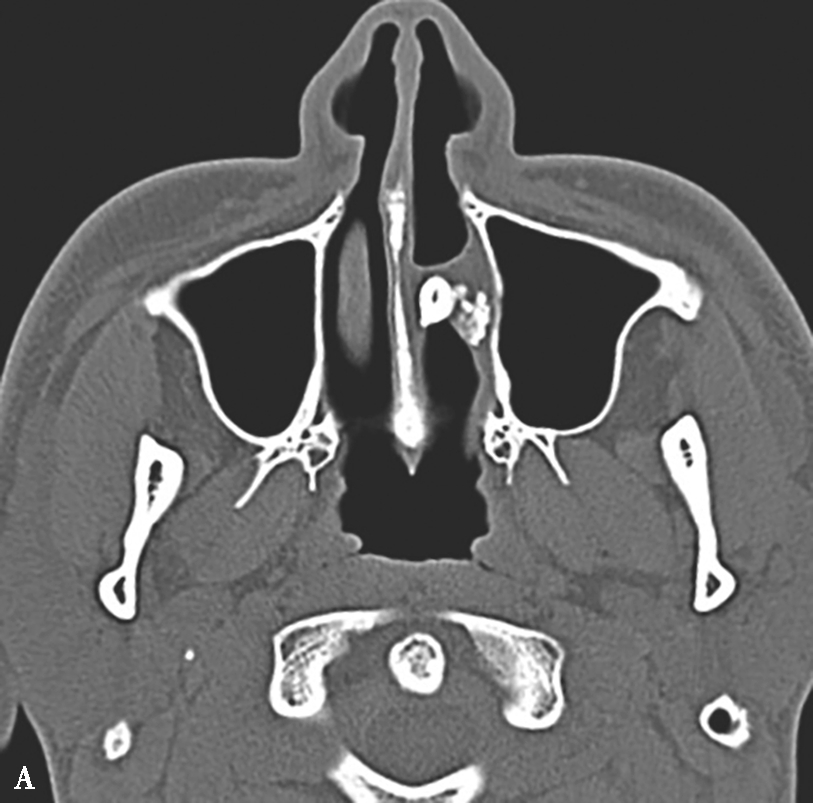

图1-3-24 嗜酸细胞增多黏液性鼻窦炎

A、B.横断面及冠状面CT骨窗,示双侧额窦、筛窦、上颌窦及蝶窦腔充填软组织影,密度不均匀,见多发斑片状磨玻璃样密度影“双重密度影”;双侧中、总鼻道见软组织影充填;C~E.横断面T 1 WI、T 2 WI及冠状面T 1 WI,示全组鼻窦窦腔充填长T 1 、混杂短到长T 2 信号影,双侧中鼻道、总鼻道及上颌窦窦口区可见小斑片状略短T 1 混杂等到短T 2 信号影